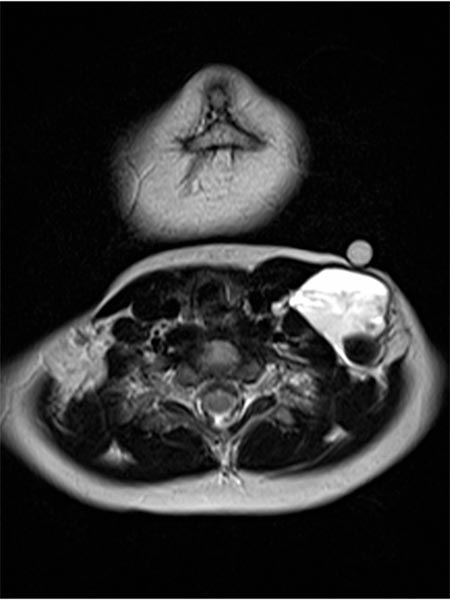

In der axialen MRT (T2-Wichtung) zeigt sich ebenfalls die dorsale Lage des größeren hypointensen Thrombus innerhalb der stark hyperintensen venösen Malformation. Zudem ein klassischer Flüssigkeits-Flüssigkeits-Spiegel innerhalb der VM. Die etwas signalärmeren, korpuskulären Bestandteile setzen sich mit der Schwerkraft nach dorsal ab (Rückenlage), das etwas signalreichere Blutserum „schwimmt“ oben (ventral) auf, dazwischen bildet sich ein Spiegel.

Die axiale MRT (T1-Wichtung) auf gleicher Höhe nach Kontrastmittelgabe zeigt eine zentrale Anreicherung innerhalb der venösen Malformation. Diese Anreicherung ist jedoch relativ langsam und erst Minuten nach KM-Injektion feststellbar und zum Zeitpunkt der Aufnahme noch unvollständig.